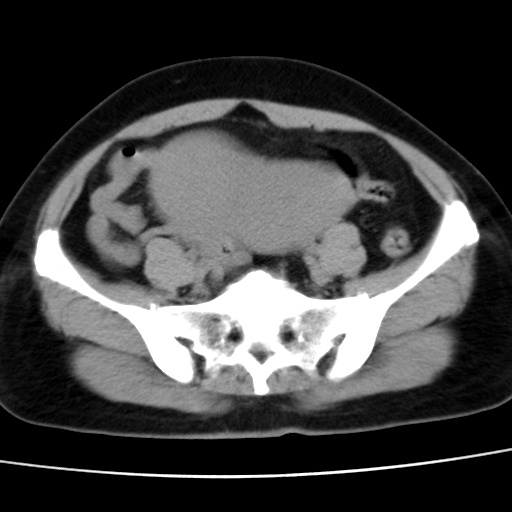

子宫多发肌瘤吗

多发性子宫肌瘤.

考虑多发子宫肌瘤,子宫直肠窝双囊性占位,另直肠周围脂肪密度增高,不知有何病史

支持考虑多发子宫肌瘤~!子宫直肠陷凹积液?

支持考虑多发子宫肌瘤~!子宫直肠陷凹积液!

子宫肌瘤,宫体部后方见液性密度影,是肠道还是子宫与直肠陷窝积液不好说,我觉得它的位置有点高

支持考虑多发子宫肌瘤!子宫直肠陷凹积液!

患者发热,而子宫直肠窝液性灶有明显边缘且局限且囊性,不除外为包裹性积液或脓肿

支持考虑多发子宫肌瘤,子宫直肠陷凹积液可能。

考虑多发子宫肌瘤

1)考虑子宫肌瘤可能性大。2)子宫后方囊性占位性病变,不排除卵巢囊肿可能。

考虑多发子宫肌瘤。子宫后方囊性占位性病变,不排除卵巢囊肿可能。